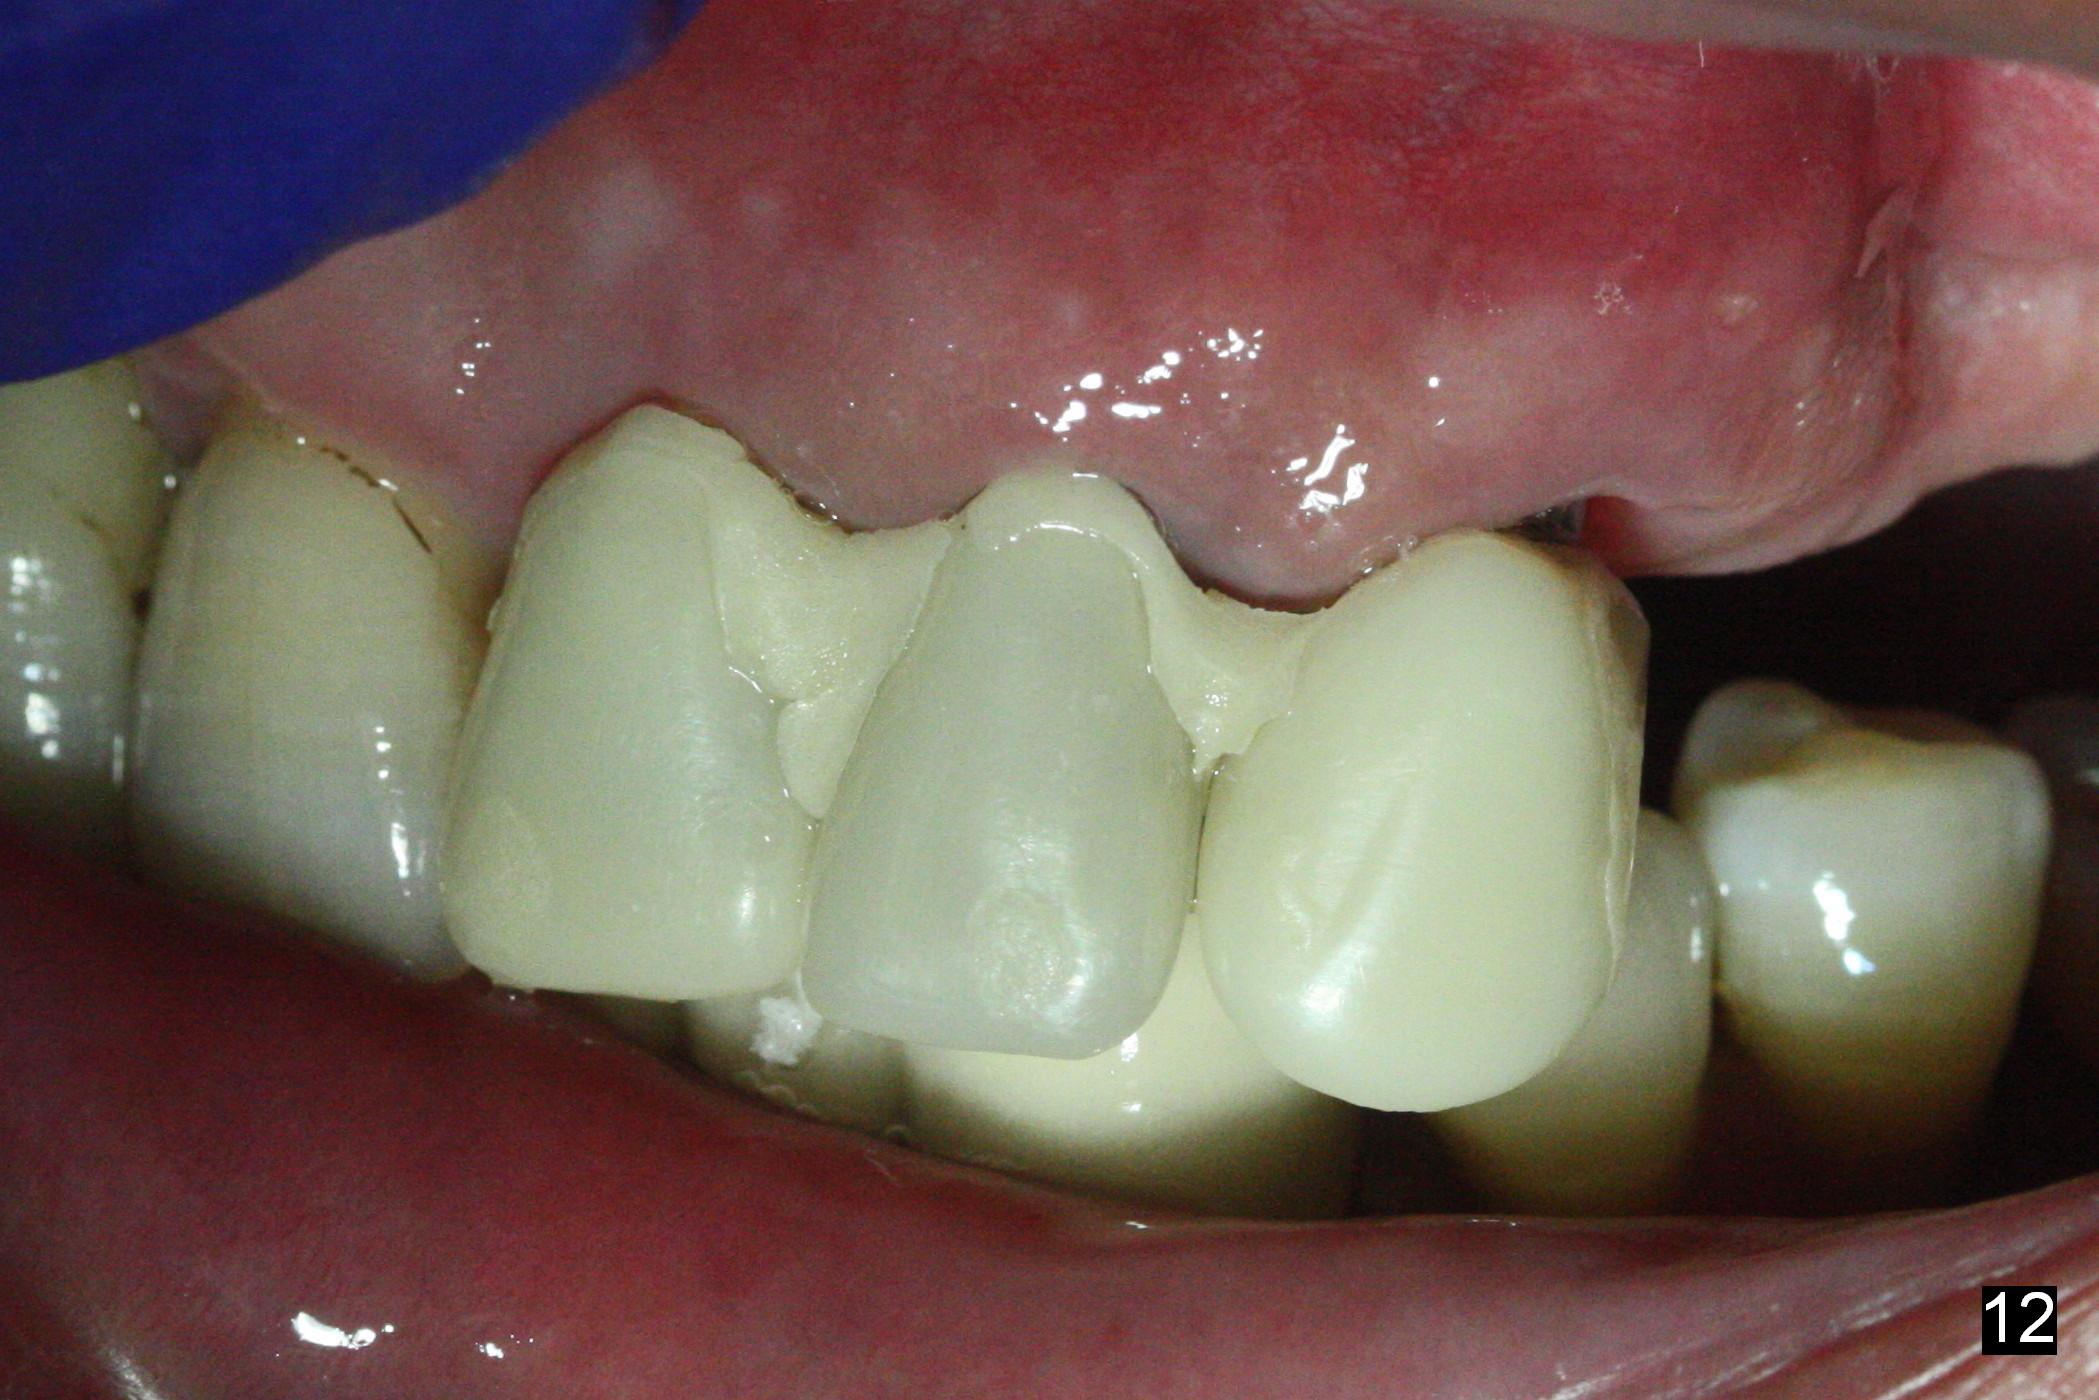

The patient returns 8 days postop, uncomfortable with overhang in the provisional (Fig.10 *). The sockets appear to be healing with loose bone graft (Fig.11) when the provisional is removed for trimming (Fig.12). Six (for #7,13) and seven (#9-11,15) months postop, the soft (Fig.13,17) and hard (Fig.14-16,18) tissues heal. It appears that the trajectory at #9,11 and 13 should be changed by using angled abutments (Fig.18,19 (panoramic X-ray taken 2 months earlier)) before provisional and final restoration.